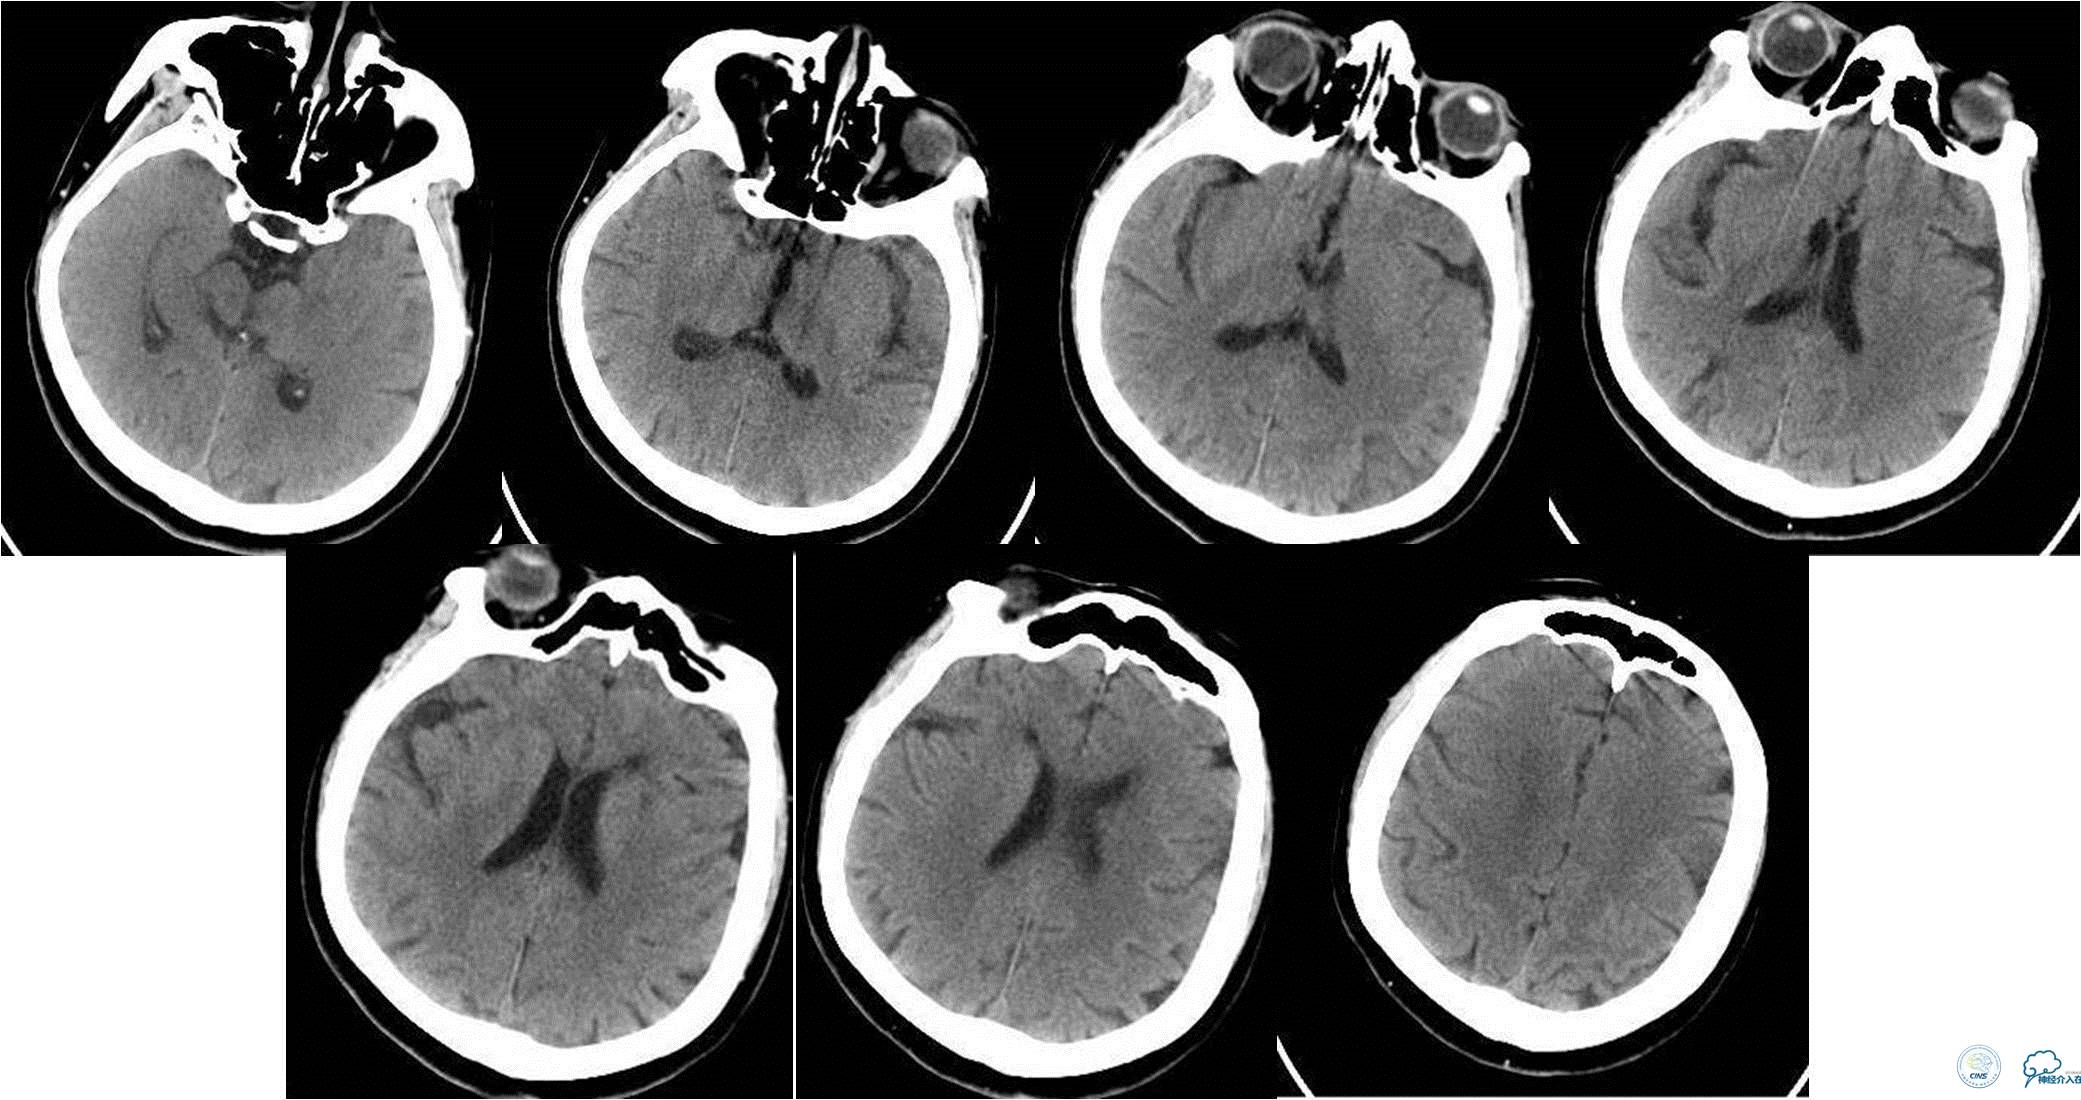

入院时颅脑CTA(发病4小时)